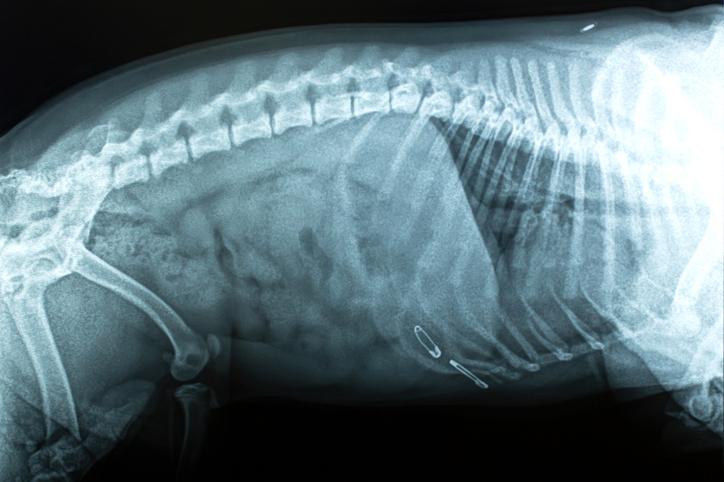

Hernias discales

La hernia discal puede ser otra causa de estreñimiento en perros y se produce cuando la degeneración de los discos intervertebrales produce el prolapso de su contenido hacia la medula espinal comprimiéndola. Según el grado de compresión y el nivel de la médula en el que tienen lugar pueden aparecer distintos síntomas:

• Dolor

• Paresia (parálisis parcial de la contractilidad de la musculatura)

• Problemas para andar o incluso parálisis

• Problemas en la micción y defecación

• Pérdidas de sensibilidad al tacto

Si el cuadro es leve puede tratarse con corticoides, en el caso contrario lo más indicado sería la cirugía. Además, hay trastornos neurológicos que también pueden afectar a este nivel.